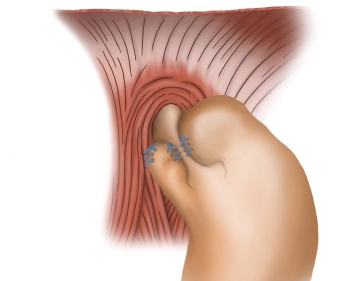

Fixation der Fundusmanschette II

-